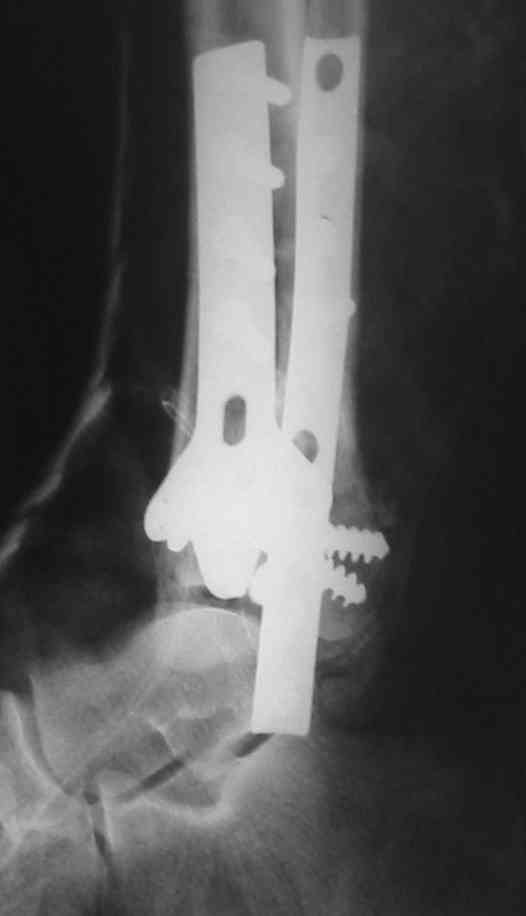

OK, Dr Driagin, Ja operiroval bolnogo po Vashemu, hotia sam ni ochen' ubezden' v itom, t.k. bolnoi otkazalsa na proch' ot ex.fix, ja emu sdelal ORIF + Kostnia plastika, snimky prelogiottsa,

Мне кажется, что все конечно далеко от идеала. Сложный перелом. Есть ощущение, что малоберцовая кость (ключ!) фиксирована с ротацией и удлинением. Снимки конечно необходимо сделать в правильных проекциях и без гипса...

В голеностопном суставе обязательны 3 стандартные ренгенологические проекции: прямая, латеральная и мортиз. Без них невозможно трактовать состояние голеностопа.

Применение шурурпов 4.5 мм и более толстых пластин крайне недопустимы. Рекомендуется низкопрофильные, контурированные пластины с шурупами 3.5 мм, а иногда те же 3.5 шурупы но с головкой 2.7 мм.

Примущества Locking plate не только механическая, и еще отсутствует раздражающий фактор на местные ткани, потому что шуруп сидит в пластине заподлицо. Если рана ушита с натяжением и имеется отек, сомневаюсь в помощи от насечек, лучше распустить рану с латеральной стороны, там больше тканей, после спадения отека можно закрыть или в

крайнем случае кожная пластика.